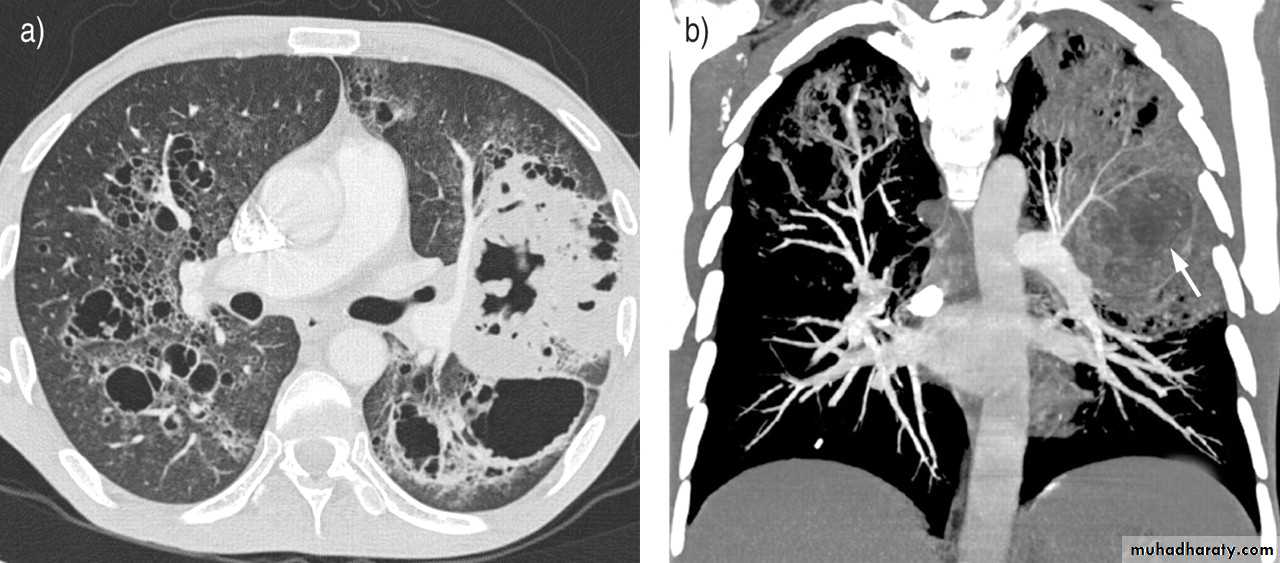

High resolution CT (HRCT) can be helpful in minimizing the differential diagnosis:

• Focal opacification favours bacteria, mycobacteria and nocardia

• Bilateral opacification favours PCP, fungi, viruses and nocardia

• Cavitation suggest mycobacteria, fungi and nocardia

• Pleural effusion suggests bacteria